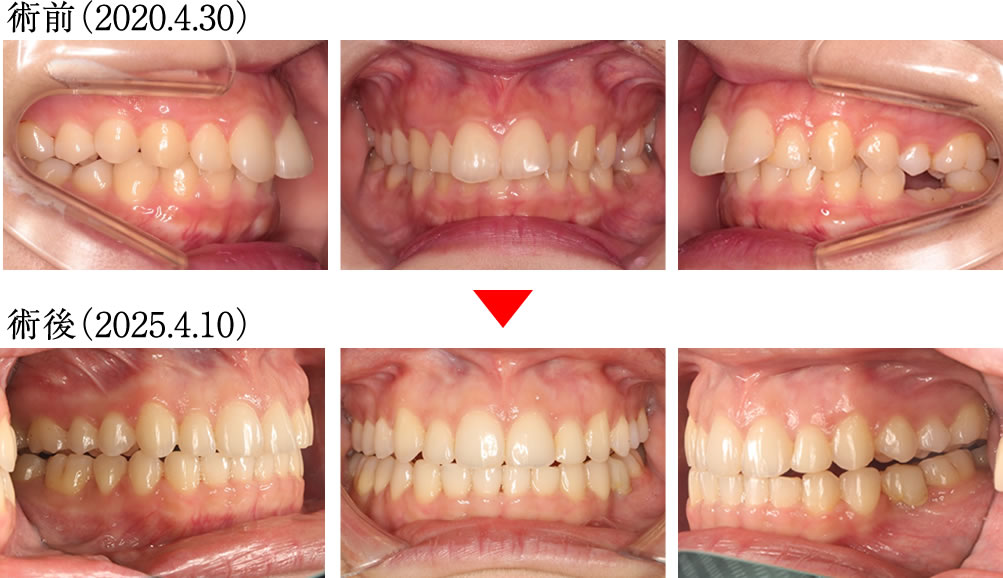

術前では、上顎の前歯が前方に傾斜しながら、深く噛みこんだ歯並びでしたが、術後は上下の歯が理想的な傾斜と被蓋関係で噛んだ歯並びになりました。

歯列が拡がったことにより、バッカルコリドー(笑った際に上の歯列と頬の内側との間にできる「黒い影」)が大きく改善されました。

術前では、歯列全体が狭く、不均衡に乱れたアーチの歯並びでしたが、術後は理想的に並んだキレイで大きなアーチになりました。